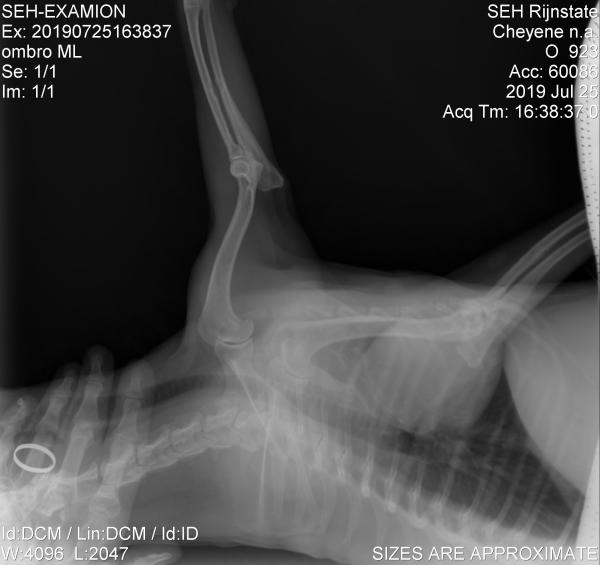

Tumores ósseos em cães

Podem ser tanto malignos quanto benignos. Entre os primeiros, como já dissemos, destaca-se o osteosarcoma, que pode aparecer a qualquer idade, tendo maior predisposição em cachorros grandes. Esses tipos de tumor em cachorro aparecem mais frequentemente nas patas dianteiras, mas também podem afetar as traseiras, as costelas ou as mandíbulas. Como sintomas desse tipo de tumor em cachorros, você poderá notar que o cachorro manca e a pata incha de maneira dolorosa. Costumam se espalhar até os pulmões.

Por outro lado, entre os tumores ósseos benignos estão os osteomas, na cabeça e face, e os osteocondromas, que afetam cachorros jovens nas costelas, vértebras, extremidades, etc.

Neste caso, assim como no restante dos tumores em cachorros, para chegar ao diagnóstico são realizados exames como os de sangue, ultrassonografia, radiografia ou tomografia computadorizada. A biópsia pode confirmar o diagnóstico.